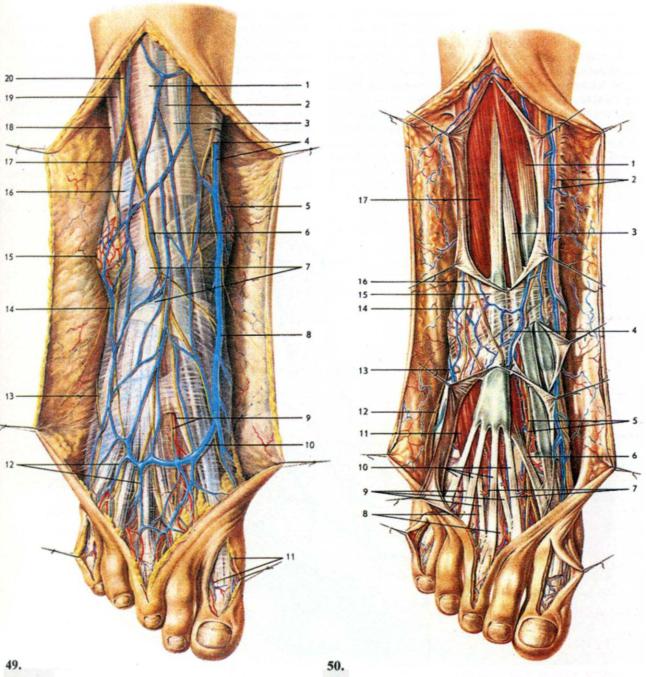

Анатомия голеностопа: Сухожилия и их строение